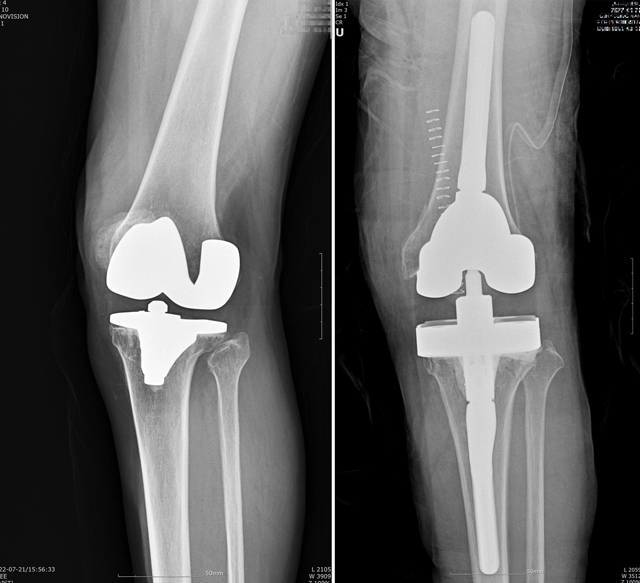

남편은 근위경골절골술(HTO)과 카티스템 이식을 동시에 받았습니다.

절골술은 간단히 말해, 무릎 아래쪽 뼈를 살짝 잘라 각도를 교정하는 수술입니다.

이걸 통해 체중이 실리는 축을 바꾸면, 닳아버린 안쪽 연골의 압력이 줄어듭니다.

그 상태에서 줄기세포를 이식하면, 새 연골이 자랄 수 있는 안정된 환경이 만들어집니다.

수술 후 2주는 통증이 심했고, 6주간은 부분 체중만 실을 수 있었습니다.

걷는 연습을 다시 해야 했죠.

하지만 3개월이 지나자 놀라운 변화가 왔습니다.

무릎이 덜 붓고, 계단을 오를 때 ‘쑤시는 느낌’이 사라졌습니다.

6개월 후 MRI에서 연골재생 부위가 선명히 보였고,

의사도 “정상적인 회복 경과”라며 미소 지었습니다.